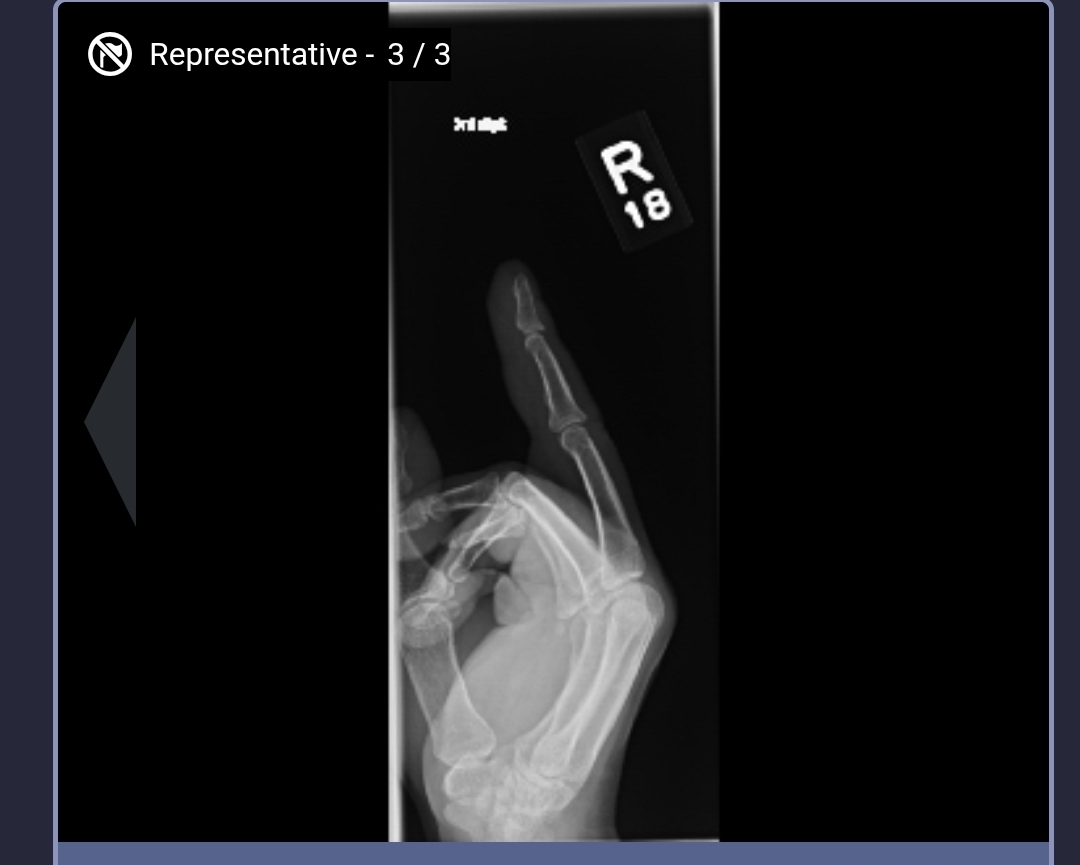

Went to the ER because I had an infection in my middle finger. This was my X-ray.